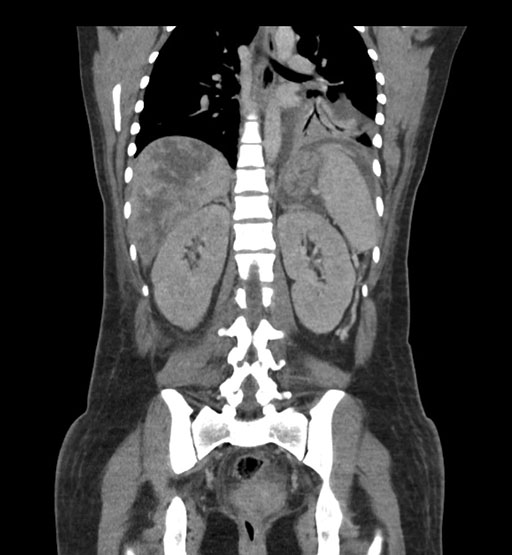

Coronal Arterial